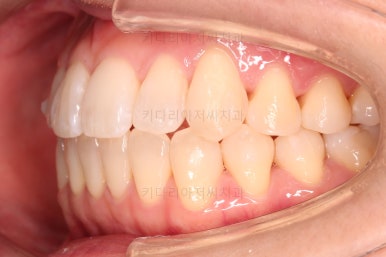

1. 초진

초진 시 입안의 모습입니다.

덧니가 눈에 띄고요.

맞물림이 긴밀하지 못한 상태였습니다.

전반적으로 약간 삐뚤지만 많이 심하다고 보긴 힘들었습니다.

덧니가 있는 방향으로 치열들이 쏠리고 틀어져 중앙선이 맞지 않는 양상이었습니다.